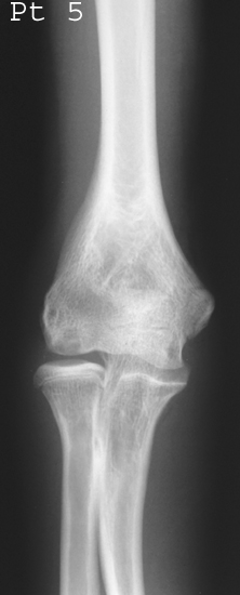

Most common site of Osteochondritis Dissecans?

Medial femoral condyle (75%).

How is it diagnosed radiographically?

MRI/CT for cartilage lesions; X-ray shows fragments and site of origin; tunnel view for knee.

What stage is this disease at?

Stage 4